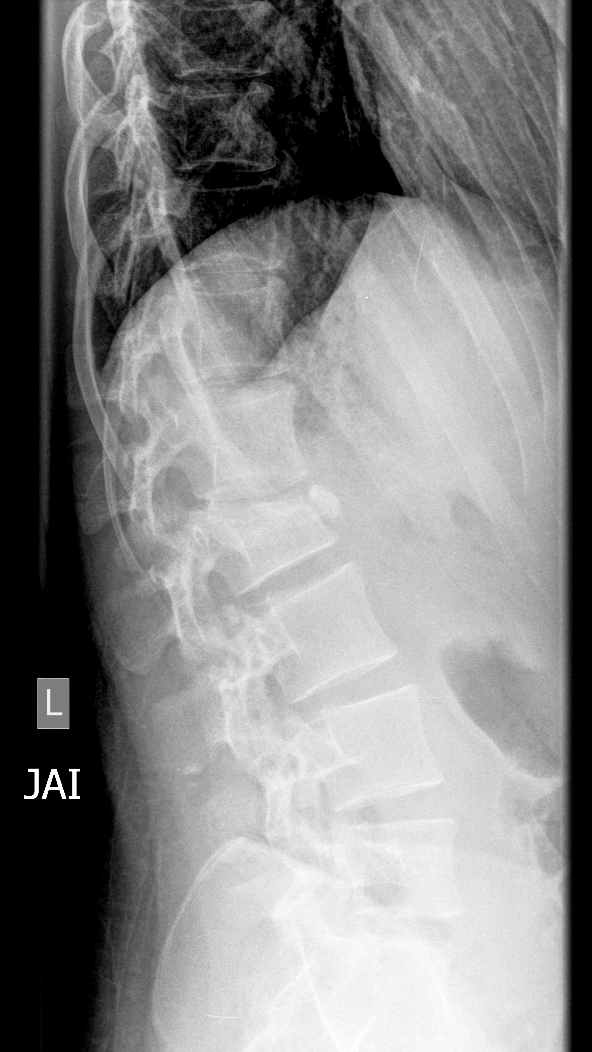

Section 1 Submit Findings CB1550 Findings Skeletal Survey - Technique Check Skull AP/Lat Yes No Cervical and Thoracolumbar spine Yes No Chest X-Ray Yes No Ribs – Left/Right Oblique Yes No Abdominal X-Ray Yes No Pelvis with both hips Yes No Bilateral Humerus, Forearm, Hand Yes No Bilateral Femur, Tibia/fibula, feet Yes No Any additional lateral views of the extremities Yes No The exam is over or under penetrated. Yes No The exam may or may not be limited by overlying structures or soft tissues, body habitus, patient positioning, support devices, or motion. Yes No The area of concern is indicated by the patient, technologist, or care provider. Yes No The area of concern is included on the exam. Yes No Soft Tissues There is soft tissue swelling, indistinctness of fat/muscle planes, gas, or laceration in the area of clinical concern. Yes No There is an effusion, fat pad displacement, or fat fluid level. Yes No There is a radiodense or lucent foreign body. Yes No There are other densities, calcifications, post-surgical changes, or support devices in the soft tissues. Yes No Any support lines/tubes. Yes No Bone There is a break or interruption of the continuity of the cortical or cancellous bone. Yes No There is overriding of the trabeculae with apparent sclerosis. Yes No There is displacement of a fracture fragment. Yes No There is bowing of the bone in addition to the fracture at the apex of the bowed bone concerning for the greenstick. Yes No There is a spiral fracture of the leg concerning for toddler’s fracture. Yes No There is abnormal angulation or bulging of the cortical surface relative to the normal cortex which could be from a buckle or torus fracture. Yes No There is a displaced fragment which may be from avulsion by a tendon, ligament, or joint capsule or from a comminuted or other fracture. Yes No The stress trabeculae or other trabeculae of the cancellous bone are interrupted or otherwise abnormal. Yes No There is subperiosteal or endosteal reaction which could indicate a healing or subacute fracture or other abnormality. Yes No There is hard/soft callus formation. Yes No There is remodeling of the bone. Yes No There is a corner fracture or metaphyseal lesion that could be from nonaccidental trauma. Yes No There are multiple fractures of different ages. Yes No There are vertebral body/spinous process fractures. Yes No There are rib fractures. Location - posterior or lateral. Yes No There is scapular/sternal fracture. Yes No There are fractures of the digits. Yes No There are wormian bones. Yes No There are intrasutural bones. Yes No There is metaphyseal abnormality (lucencies, increased density, erosion) which may be from something other than injury such as stress, metabolic disease (e.g. rickets with loss or distortion of the zone of the provisional calcification), neoplasm (e.g. leukemia), heavy metals, inflammation, or infection. Yes No There are metaphyseal spurs. Yes No There are bony deformities involving multiple bones. Yes No The bones are gracile. Yes No There are non-healing fractures. Yes No There is/are focal or multifocal lytic/lucent, blastic/sclerotic or mixed density lesion(s) or other abnormality. Yes No Overall bone density is increased or decreased with or without thinning or thickening of the cortical or cancellous bone. Yes No Growth plates, ossification centers, apophyses The growth plate(s) is/are abnormal. Yes No There is widening of the physis from a fracture with or without displacement of the epiphysis (Salter-Harris I). Yes No There is a fracture through the physis which then extends into the metaphysis with or without angulation or displacement (S-H II). Yes No There is a fracture through the physis which then extends into the epiphysis and is intra-articular, with or without angulation or displacement (S-H III). Yes No There is a fracture through the metaphysis, physis, and epiphysis which extends into the joint space with or without angulation or displacement (S-H IV). Yes No There is narrowing of the physis from a compression fracture (S-H V). Yes No The apophysis, epicondyle, secondary ossification center, or accessory ossicle is displaced or otherwise abnormal. Yes No The ossification centers are underdeveloped. Yes No Joints and alignment There is an effusion, fat pad displacement, or fat fluid level. Yes No The epiphysis or subchondral bone is fractured, interrupted, flattened, compressed, impacted, displaced, or otherwise abnormal. Yes No There is an intra-articular loose body or chondrocalcinosis. Yes No The joint is widened, narrowed, dislocated, malaligned, or incongruent. Yes No There is pseudoarthrosis. Yes No Other findings There are developmental changes or other anatomic variants or other existing conditions that may or may not be contributing to symptoms which can or should be further evaluated non-emergently or are otherwise incidental. Yes No The remainder of the exam is abnormal for age. Yes No The lungs show focal airspace opacity. Yes No There is pneumothorax. Yes No There is organomegaly. Yes No There is intra-abdominal calcification. Yes No There is displacement of the bowel loops. Yes No There is free intraperitoneal air. Yes No The bowel loops are dilated/obstructed. Yes No There is paraspinal soft tissue abnormality. Yes No